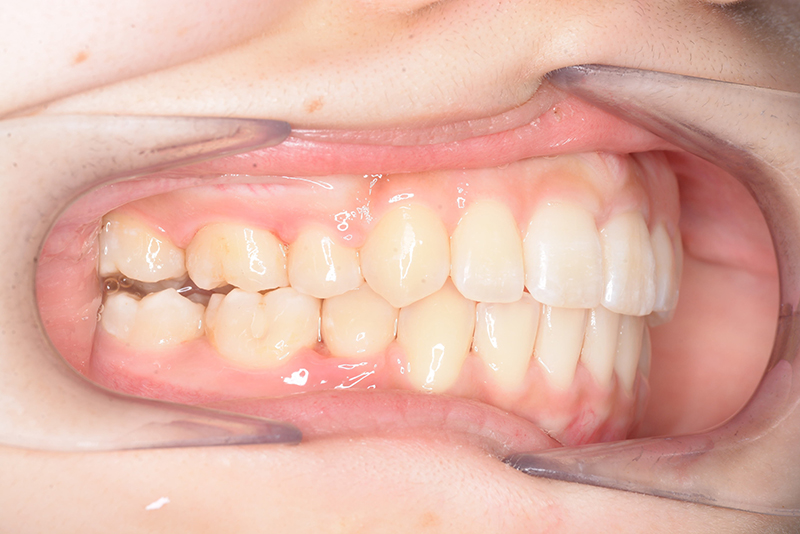

| 口腔内所見 | over jet 3.8mm、over bite 30mm、臼歯関係I級、上下顎前歯部に叢生が認められ、下顎正中は右側へ4.5mm偏位していた。左上5はCRの治療痕が認められた。 |